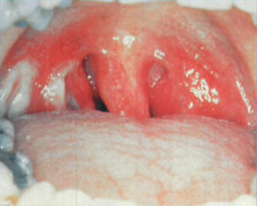

淋菌性結膜炎也稱淋病眼或淋菌性膿漏眼,是一種極為劇烈的急性化膿性結膜炎。本病的特點為高度眼瞼、結膜充血水腫及大量膿性分泌物,如治療不及時,將短時間內發生角膜潰瘍及穿孔,導致失明的嚴重后果。

淋菌性結膜炎病原菌為淋球菌,又稱奈瑟淋球菌,是一種革蘭氏陰性雙球菌,常存在于多形核白細胞的胞漿內。淋球菌離開人體后不易生長,對理化因子的抵抗力弱,攝氏42度存活15分鐘,50℃只存活5分鐘;在完全干燥的環境中1~2小時即死亡,但在不完全干燥的環境和膿汁中則能保持傳染性10余小時,甚至數天。

人類是淋球菌唯一的自然宿主,淋病主要由性接觸而傳播。淋球菌侵入泌尿生殖系統繁殖,男性發生尿道炎,女性引起尿道炎和子宮頸炎。如治療不徹底,可擴散至生殖系統。胎兒可經產道感染造成新生兒淋病性急性結膜炎。人類對淋球菌無自然免疫力,均易感,病后免疫力不強,不能防止再感染。